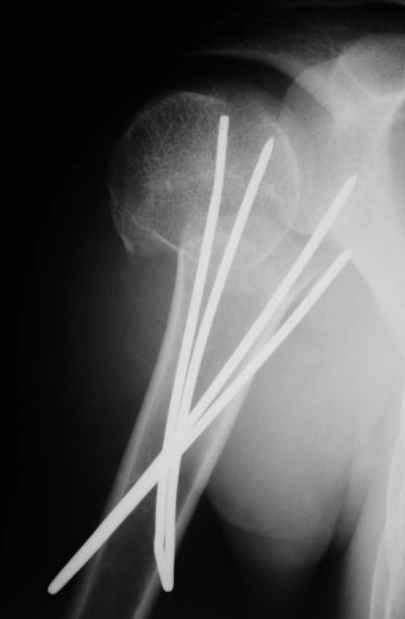

Спасибо за участие в дискуссии -перелом шейки плеча, для себя я прояснил многие технические моменты...

Посылаю послеоперационные Рг граммы.

Я и сам доволен результатом. В предпоследнем письме я кратко описал ход операции - закрыто репонировать не удалось( 2 недели с момента травмы и 1 неделя после неудачной репозиции) после удаления пучков спиц, пришлось сделать - 2см разрез на уровне перелома и с помощью периостального элеватора (золотое правило механики) *одеть* головку на дистальный отломок.

Спицы проводил через старые отверстия, вращая пучок импактором- направителем при его введении в головку.

Поздравляю, получилось просто замечательно. Если можно, расскажи чуть подробнее, как делали - как вправляли, как вводили спицы, поворачивали ли их?